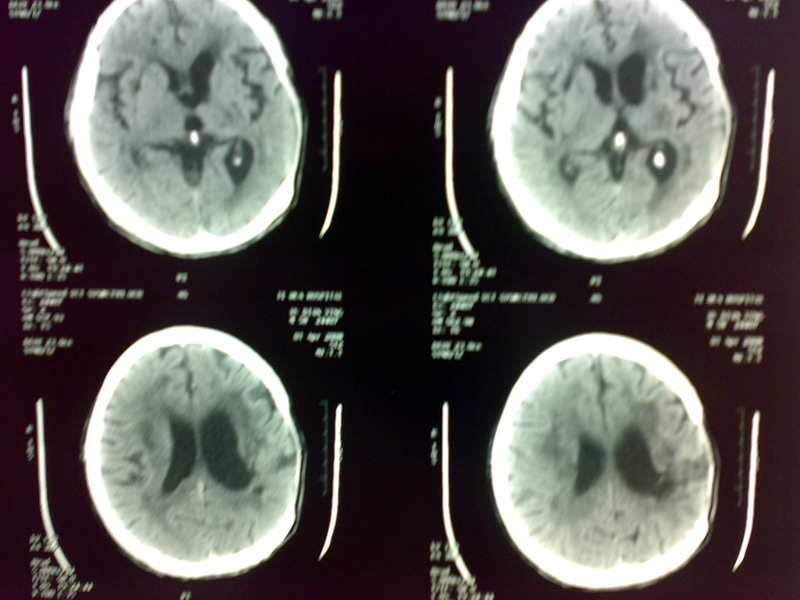

标题: CT12613:男 60 5个月前脑出血手术 现头外伤来诊 [打印本页]

标题: CT12613:男 60 5个月前脑出血手术 现头外伤来诊

脑出血术后改变,皮层下动脉硬化性脑病,腔梗,脑萎缩

考虑:1、左侧脑出血术后改变;

2、脑白质稀疏症。

1、脑出血术后改变 2、皮质下动脉硬化性病变 3、未见外伤性改变

2包括多发性脑梗塞、脑萎缩及脑白质病,再列出似有画蛇之嫌!

左侧脑出血术后改变,两侧基底节区多发脑软化灶及腔梗,脑白质变性,脑萎缩

左侧脑出血术后改变,两侧基底节区多发软化灶及腔梗,脑白质变性,脑萎缩

1、脑出血术后改变;  2、皮层下动脉硬化性脑病。